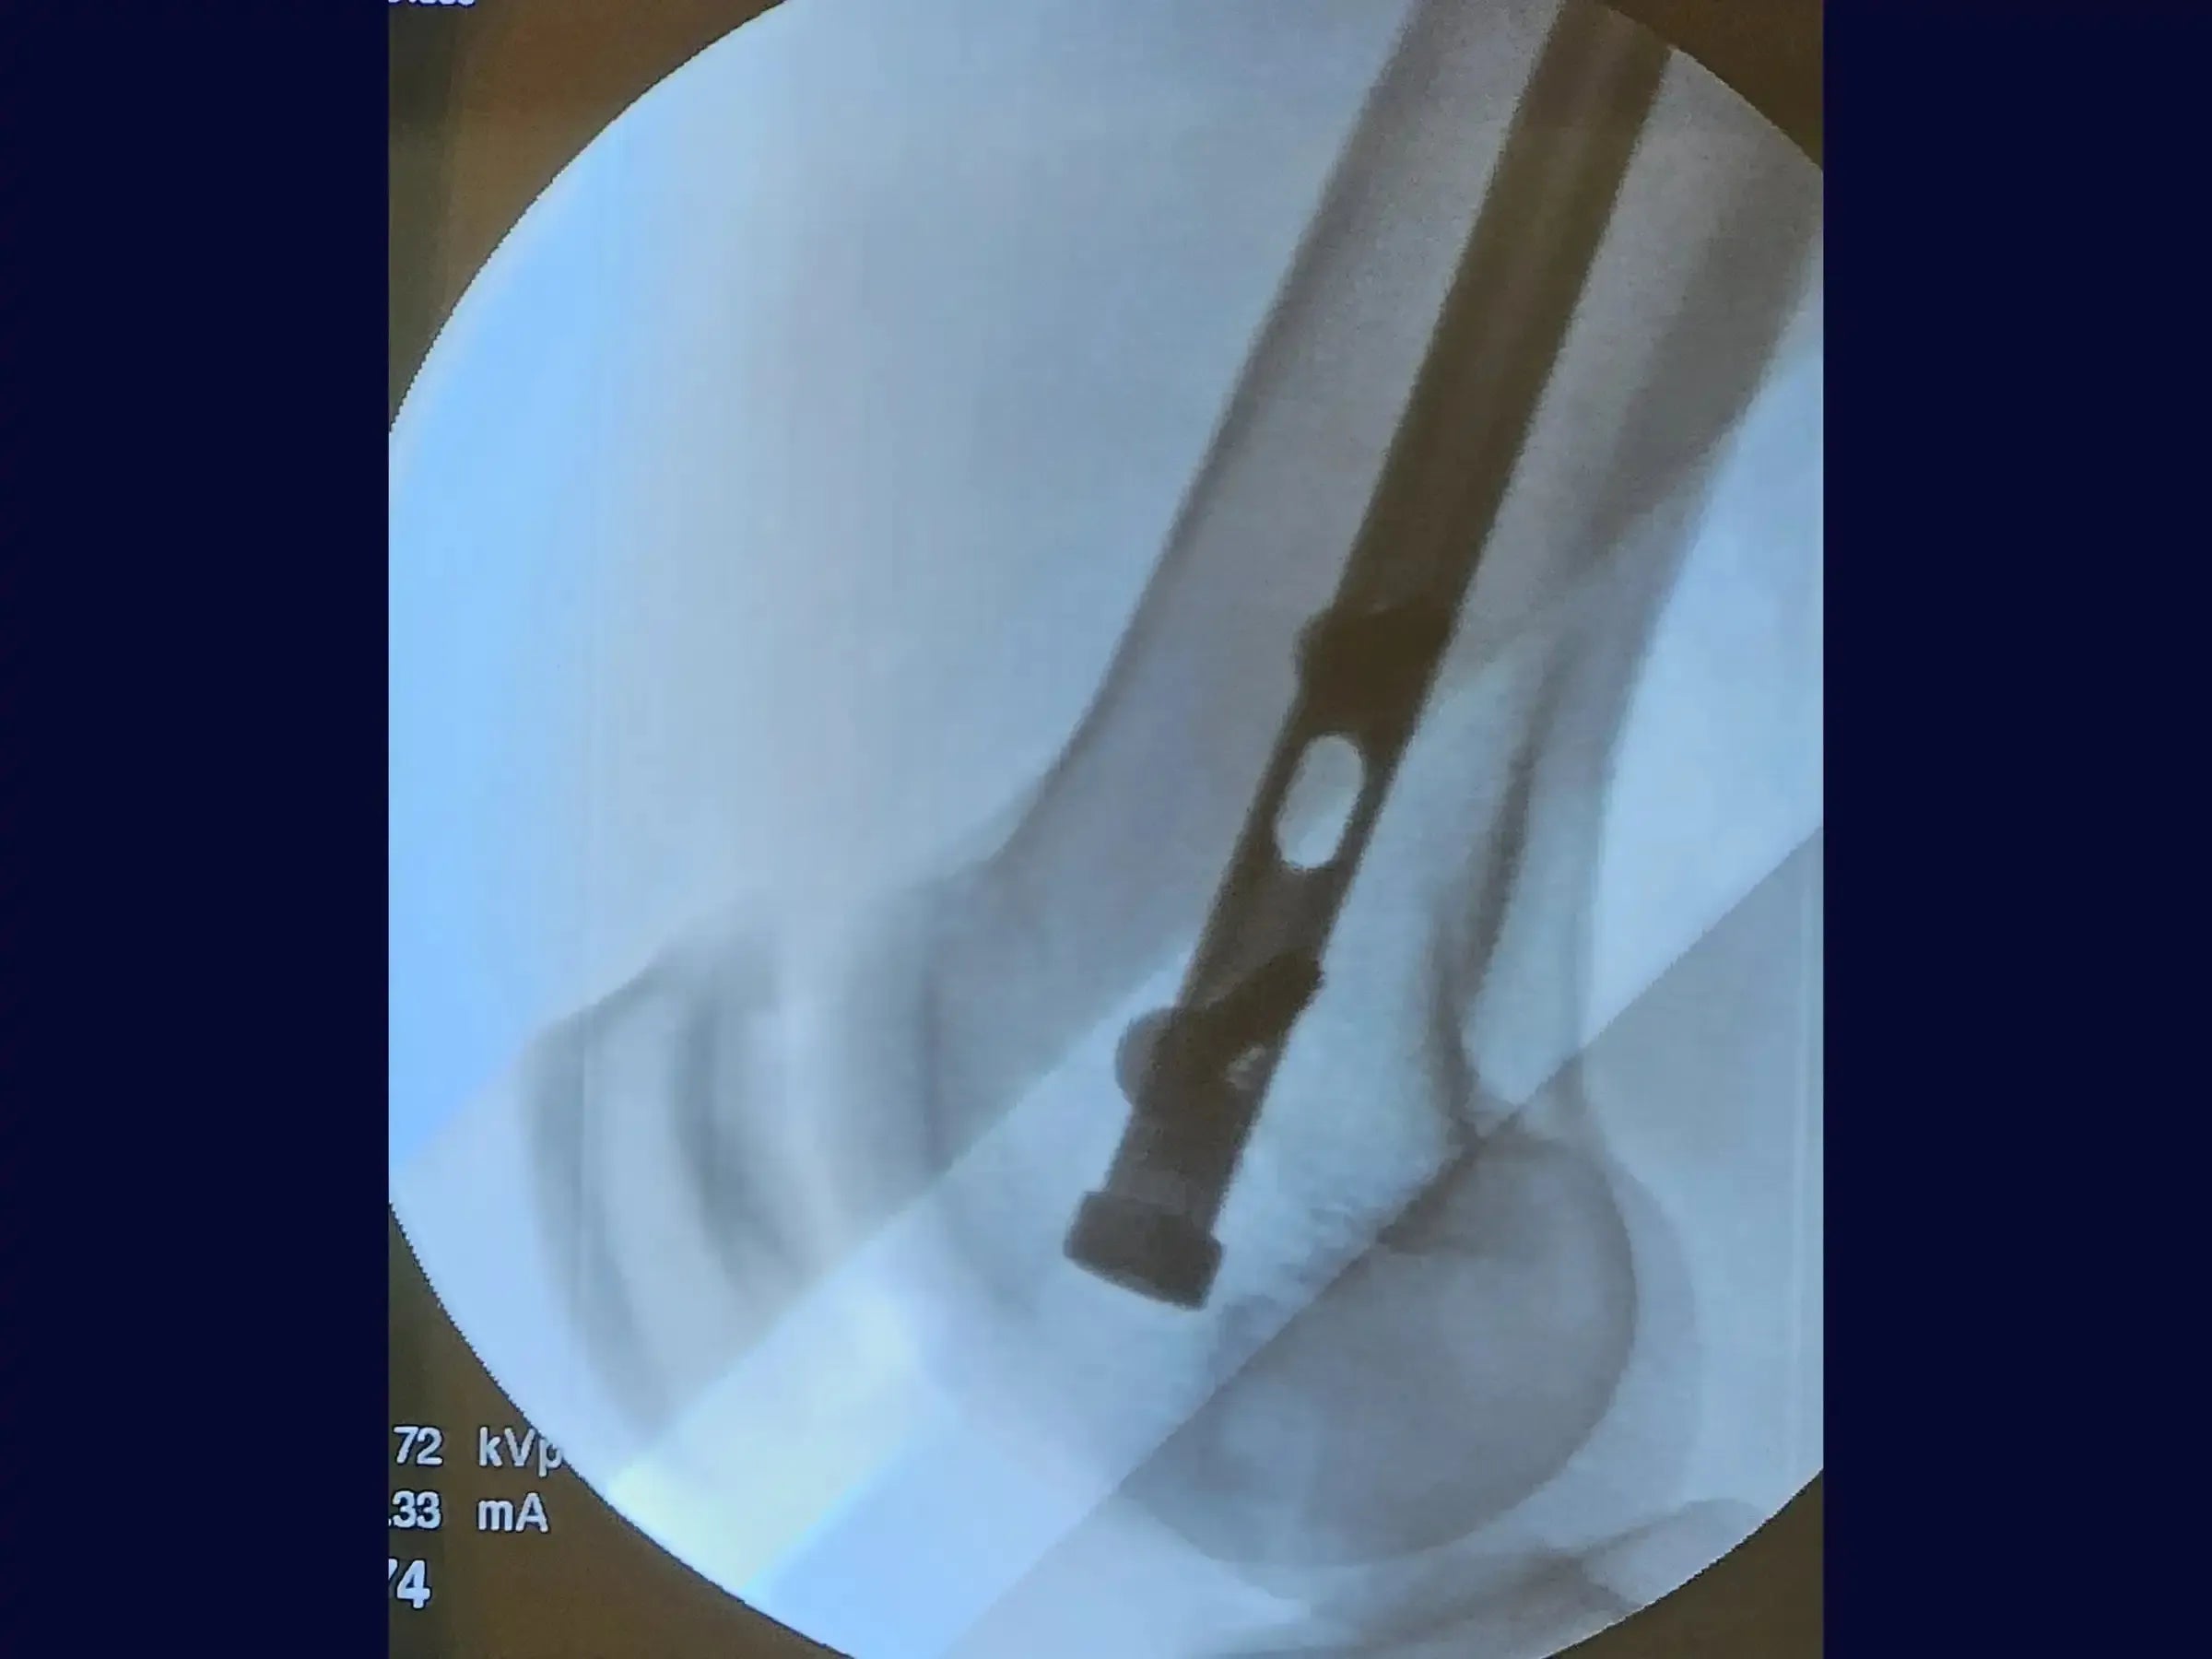

- Bloqueio Distal Preciso: Domine a confecção dos parafusos de bloqueio distal utilizando guia específico, broca e medidor. Compreenda a necessidade de rotação interna do joelho para avaliar o tamanho correto do parafuso devido ao formato trapezoidal do fêmur distal, prevenindo falsas impressões.

- Bloqueio Proximal Minimamente Invasivo: Realize o bloqueio proximal sob fluoroscopia, com acesso minimamente invasivo, assegurando a conferência do perfil através da rotação da perna para certificar o tamanho correto do bloqueio, mesmo com grande massa muscular.

- Resultados Otimizados: Obtenha resultados cirúrgicos onde a haste está posicionada acima do pequeno trocânter e seguindo a linha de Blumensatt, sem proeminências no joelho, permitindo certa mobilidade no pós-operatório.